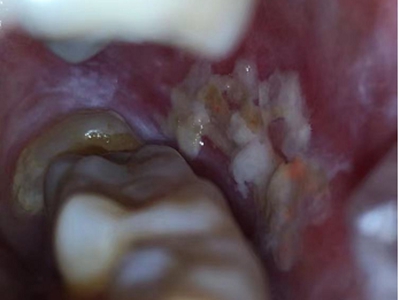

牙龈

白斑

口腔白斑病牙龈皱纸状白斑图

口腔白斑病表现为牙龈外侧有大片皱纸状白斑,呈红白间杂的损害,边界清楚,表面高低起伏,状如白色皱纸,粗糙柔软,患者有刺激痛。